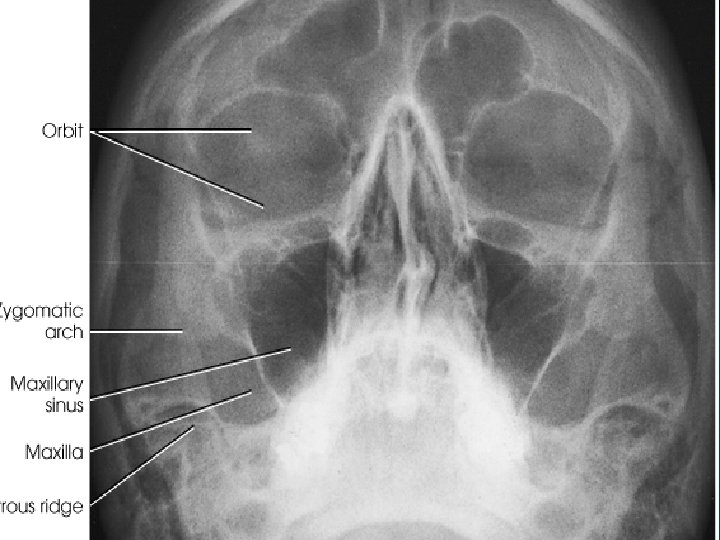

Waters Radiograph n Distance from lateral border of skull and orbit equal on each side n Petrous ridges projected immediately below maxillary sinuses

Reverse Waters Radiograph n Distance from lateral border of skull and orbit equal on each side n Petrous ridges projected immediately below maxillary sinuses